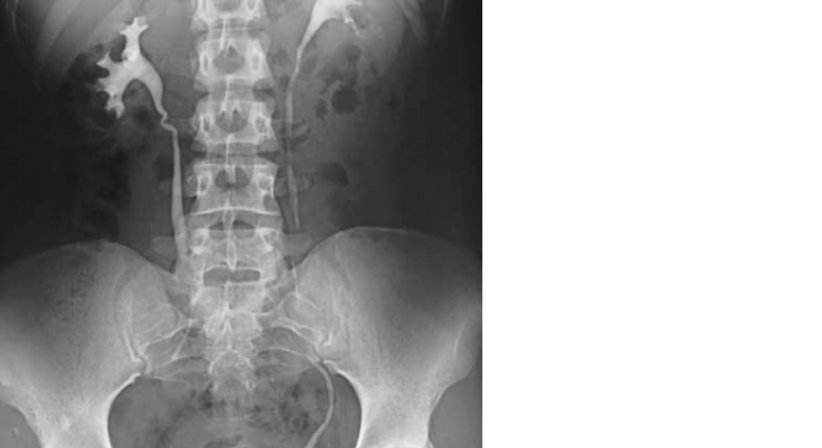

Im Rahmen von Röntgenuntersuchungen können durch die Verabreichung spezieller Kontrastmittel Innere Organe untersucht werden.

Zur Untersuchung der Nieren oder der Beinvenen wird Kontrastmittel in eine Vene injiziert.